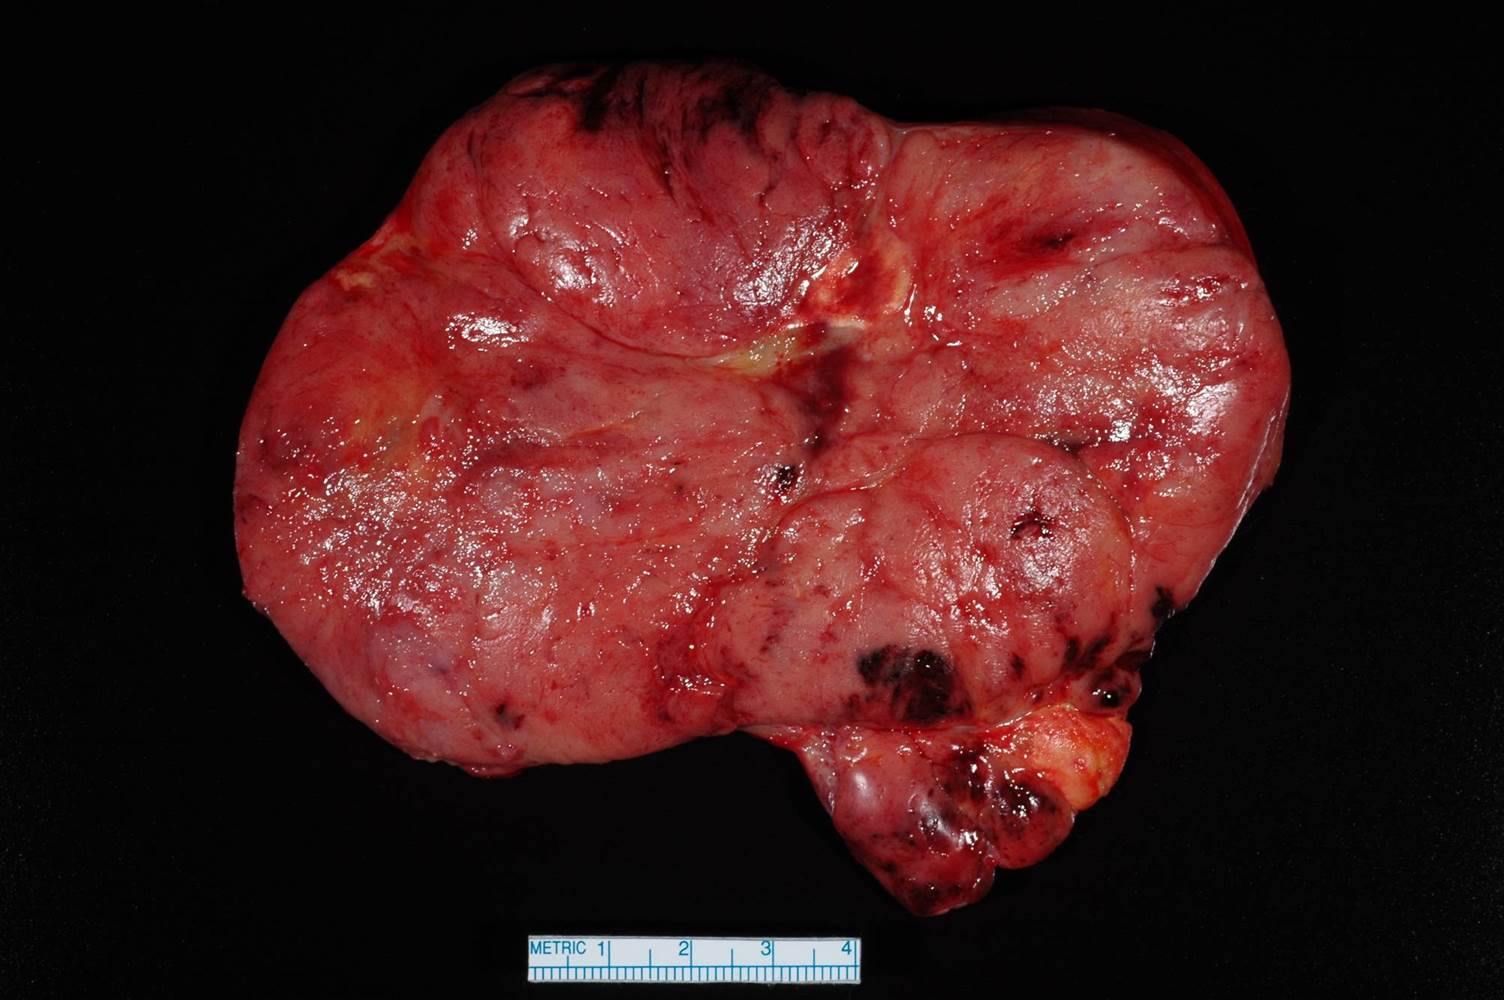

Case ID: 702

Consensus grade: I would not grade this tumor

chromophobe |

| Pathologist 17 | WHO/ISUP grade 4 | Borderline lower |

chromophobe RCC-grading? |